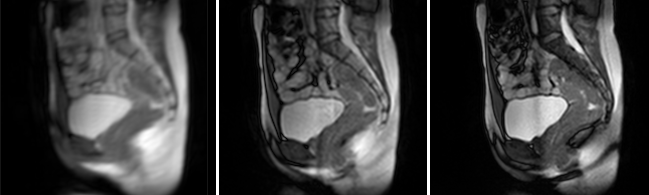

Supporting materials caption

Animations describing the volume deformations of 2 observed bladders. Global displacement is not reproduced, but colormap provided a visualization of the local surface changes. First column: reconstruction of the 3D dynamic volumes (blue) on the skeletons from the multi-slice acquisition segmentations (red). Second column: Projection on the static volume of the Jacobian maps associated with the registrations generating the reconstructed complete dynamic volumes. Third column: Single projection of the map on the static volume. Volumes from each geometric configuration were placed in a common time frame but the volume rate per second is different and each configuration was imaged during independent acquisition. For each representation, the anterior (left) and posterior (right) views are provided.